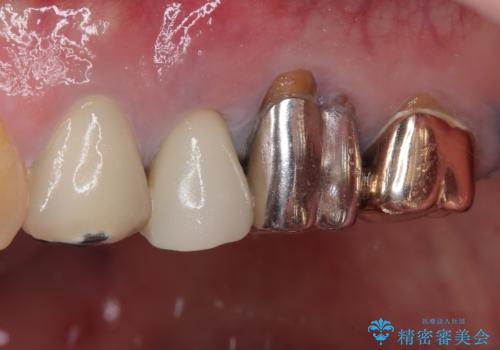

抜歯即時埋入後にはずっと気になっていた排膿が消え、痛みも腫れも特になく、3ヶ月という短期間で無事に治療を終えることができました。

破折した奥歯 抜歯即時埋入インプラントによる補綴治療